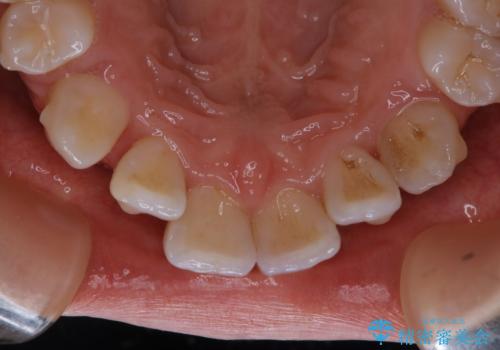

- インビザラインでのマウスピース矯正中に着色が気になるとのことでした。着色が全体的に付着していたためPMTC60分コースを行いました。

PMTC(保険外治療)は、毎日の歯磨きで落としきれない汚れや、コーヒ、紅茶・タバコのヤニなどの着色も除去します。目には見えない歯と歯の間・歯肉の境目・インビザライン中はアタッチメント周囲などに残っているプラーク(歯垢)もしっかり取り除きます。PMTCでは専門的な機械や材料を使用して、徹底的に汚れを除去するため、虫歯・歯周病・口臭予防などにつながります。